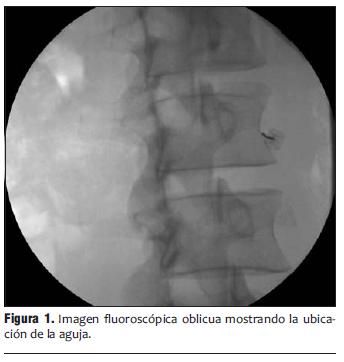

3. Procedimiento guiados a los sitios dolorosos o a estructuras nerviosas para inhibir o bloquear el dolor, conde alivió seguridad y bajo condiciones orientadas con fluroscopia (Rxs) y por medio de ultrasonido, y de vanguardia con radiofrecuencia pulsada que extienda el tiempo de semanas a años